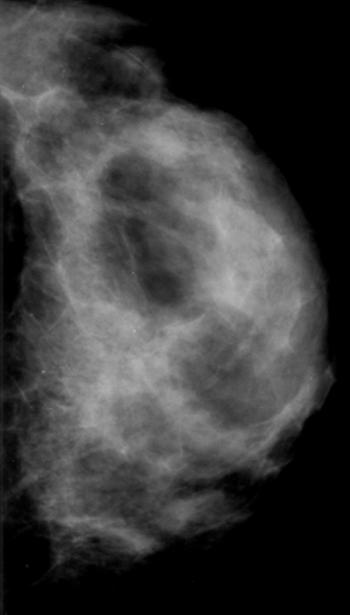

Endometrial stromal sarcoma (ESS) is a rare malignant tumor of the endometrium, occurring in the age group of 40-50 years.